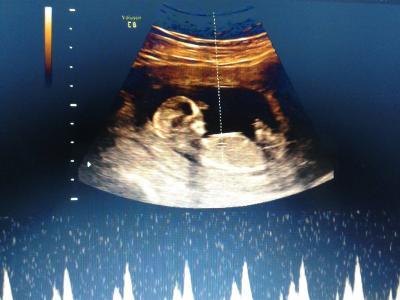

Alles super das baby ist zeitgerecht entwickelt Wir haben eine cd mit Videos und bildern mit bekommen für 5 € :) Und man konnte noch nicht sehen was es wird Vielleicht In zwei wochen zur untersuchung beim Frauenarzt Die bilder sind aus der cd hab die abfotografiert vom Laptop

da guckt es gerade in die kamera ;)

Bild zu